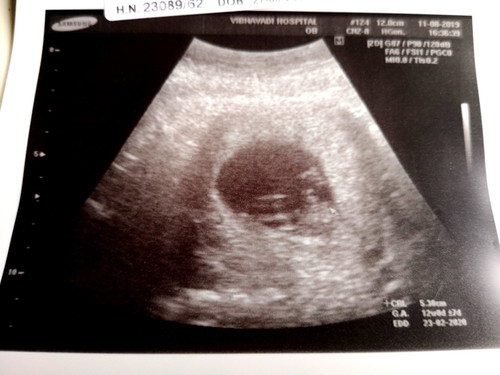

12w. มีติ่งจู๋โผล่ หมอบอกว่ามีโอกาสหดกลับได้ ยังไม่ยืนยันผช.100% แม่ๆคนไหนเจอแบบนี้แล้วกลายเป็นผญ.มั้ยคะ? #จะญ./ช.แม่ก็รัก

กลัวเหมือนกันค่ะ ซาวด์ตอน24วีค หมอบอกผู้ชาย กลัวจะหดเข้าไป เพราะไม่รู้ที่เห็นน้องอยู่ในท่าไหน ตรงลูกศรที่หมอชี้ เห็นแม่ๆหลายท่านบอกว่าซาวด์ได้ชายคลอดได้หญิงกันเยอะมาก

ของเราซาวด์ตอน 12 week เห็นแหลมๆ เหมือนจะมีช้างน้อย แต่พอตรวจเลือดแม่ (ตรวจ nift) ตอน 16 week เจอแค่โครโมโซม x จ้า พอซาวด์อีกทีไม่มีแหลมๆ แล้ว 😂

บางทีอาจจะยังเล็กมากๆหมอเลยยังไม่กล้าฟันธงค่ะ เพราะอาจจะเป็นสายสะดือก็ได้ รออัลตราซาวด์อีกรอบนะคะแม่ น่าจะชัวร์ค่ะ

ใช่ค่ะติ่งแบบนี้เห็นหลายคนบอกว่าน้องนอนกอดสายสะดือ มีโอกาสเป็นไปได้สูงค่ะ

ใจเย็นๆรอไปก่อนนะคะ น้องพึ่ง 12วีคเองค่ะ รอสัก16-20วีคค่ะ ถึงจะเห็นว่าเพศไหนชัดเจนนะคะ